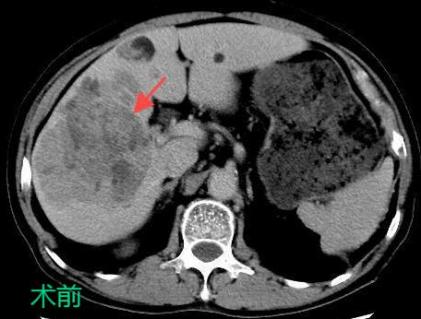

三、肝癌的介入治療

TACE/HAIC:經(jīng)肝動(dòng)脈灌注化療栓塞(TACE)、肝動(dòng)脈內(nèi)灌注化療藥物(HAIC)是在不開刀暴露腫瘤病灶的情況下,在皮膚上做直徑幾毫米的切口,在影像設(shè)備的引導(dǎo)下,導(dǎo)絲和導(dǎo)管插入肝臟腫瘤血管,注入栓塞劑和化療藥物使肝臟腫瘤內(nèi)化療藥物濃度提高,并減少全身的藥物總濃度,達(dá)到提高化療效果并減少毒副作用的目的。對于無法手術(shù)切除的巨塊型肝癌、肝內(nèi)多發(fā)肝癌病灶、肝癌結(jié)節(jié)破裂出血有良好的治療效果。

癌的介入治療